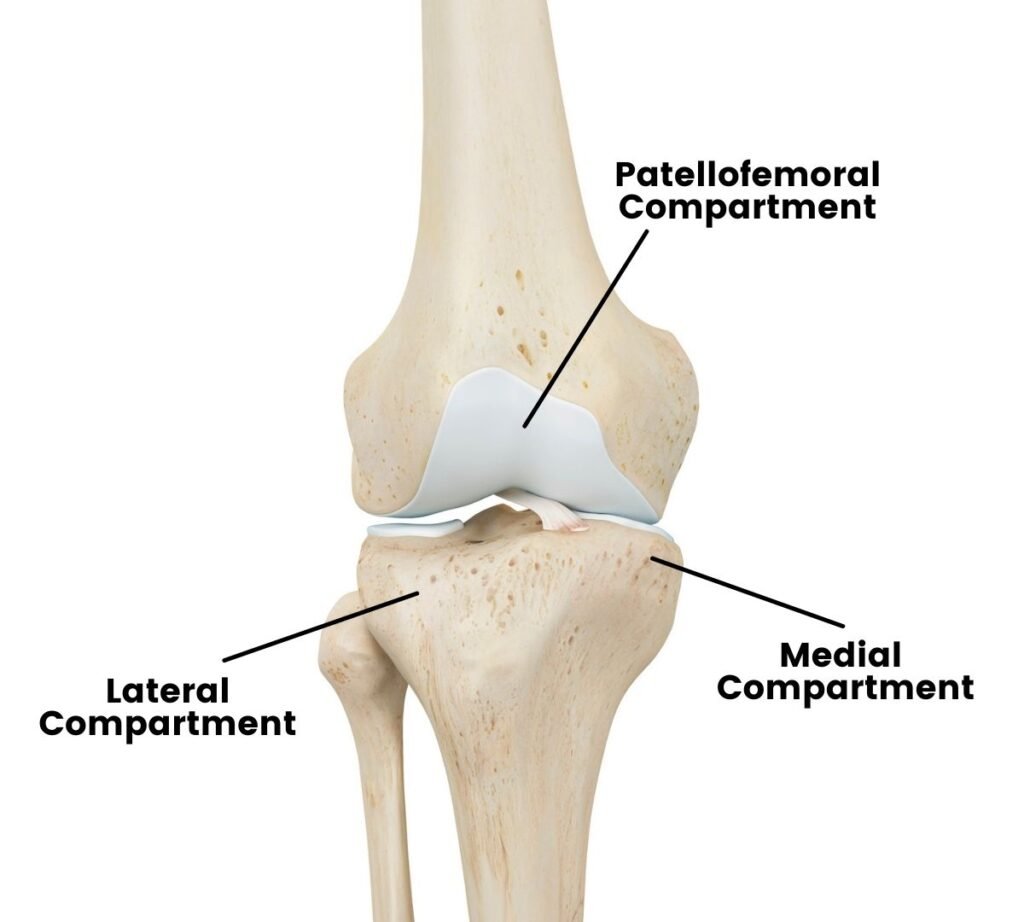

Understanding your knee joint (anatomy)

The knee is divided into three key compartments:

- Medial compartment – the inner side of the knee (most commonly affected by arthritis)

- Lateral compartment – the outer side

- Patellofemoral compartment – where the kneecap meets the thighbone

In many patients with knee osteoarthritis, only one compartment, typically the medial compartment, is damaged, while the rest of the knee remains relatively healthy. If you have arthritis limited to a single compartment, you may not need a total knee replacement. In these cases, unicompartmental (partial) knee replacement may be recommended as a less invasive alternative that preserves your native knee structures.